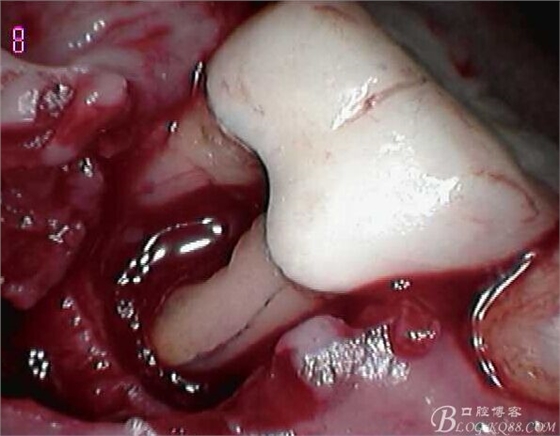

頰側(cè)翻瓣見(jiàn),頰側(cè)骨壁完全缺損,同時(shí)見(jiàn)近遠(yuǎn)中根都有縱向裂紋,

無(wú)法保留,

建議拔除C6,延期種植,

因C5遠(yuǎn)中骨壁完全喪失,

調(diào)合觀察C5,